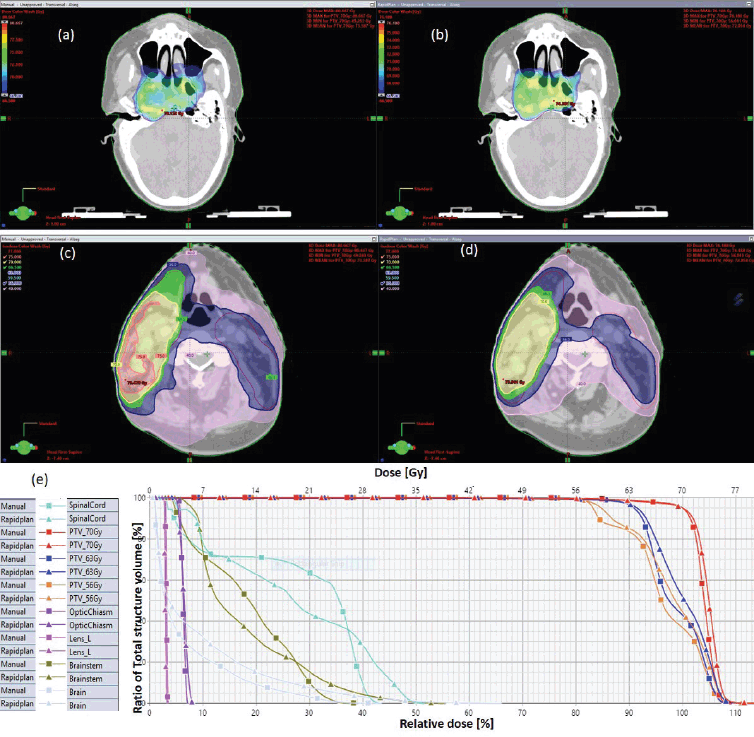

Figure 2. Typical three-dose level SIB plan for nasopharyngeal carcinoma, comparing: (a) 95% of PTV70 for VMP, (b) 95% of PTV70 for VAP, (c) colour wash – PTV56 for VMP, (d) colour wash – PTV56 for VAP and (e) DVH for VMP versus VAP showing the three PTVs and OARs.

The results showed that the prescription goal criterion of D98% ≥ 95% was achieved in all plans, with mean D98% ranging from 95.6% to 98.1% for VAPs and from 98.2% to 99.2% (p = 0.060) for the VMPs. The D2% ≤  107% criterion was fulfilled by 46/60 (76.7%) for VAPs (a mean value of 106.3% ± 1.5%), compared to 40/60 (66.7%) for VMPs (a mean value of 106.6% ± 1.3%) (p = 0.065). The dosimetric parameters analysed for the different PTV site cases are shown in Table 1. The comparison of the mean PTV (Dmax) for all cancer plans for VAPs and VMPs was not significantly different (p = 0.07). All plans achieved a conformity index (CI) greater than 0.90, and the mean CI for VAPs and VMPs for all sites was not statistically significant. The mean homogeneity index for VAPs and VMPs for all sites was not statistically significant, apart from the oesophagus and breast plans, where VMPs exhibited higher values. There were statistically significant differences (p < 0.01) in the average time to develop VAPs (29.5 ± 3.0) minutes compared to VMPs (43.2 ± 12.0) minutes, representing a 33.0% time saving. The average MU-factor was 3.0 ± 0.8 and 3.0 ± 0.2 for VAP and VMP, respectively (p = 0.21). For breast plans, the quality index (QI) ≤  0.3 criteria were fulfilled by both planning methods with mean values of 0.26 ± 0.06 and 0.16 ± 0.12 for VAPs and VMPs, respectively (p = 0.18). Figures 1 and 2 show the representative two-dose-level prostate and three-dose-level head and neck (nasopharyngeal carcinoma) simultaneous integrated boost (SIB) plans, respectively, comparing VAPs and VMPs dose distributions and corresponding dose volume histograms (DVHs). The results indicated that both computation methods achieved very good PTV coverage and OAR sparing, with VAPs showing superior protection of the rectum (Figure 1d) and larynx (Figure 2d). There were variations in the OARs’ dose constraints projected by the two methods. The dose constraints analysed for the different OARs and different site cases are shown in Table 2. There were no statistically significant differences between the VAPs and VMPs calculated results for all case sites, apart from the breast and prostate cases.

Table 2 indicates that, on average, the dose constraints for head and neck OARs like optic chiasm, eye lens, brain stem and spinal cord were adequately achieved by both methods, as explicitly reflected in Figure 3a. The same was true for prostate cases, where all pelvic OARs are within limits, apart from the bowel bag. Furthermore, although both methods achieved the rectum: V50Gy ≤ 50% constraint, VAPs predicted much lower doses than the corresponding VMPs (Dmean of 16.5 Gy versus 30.6 Gy and p = 0.01). This implies that the auto-plans provide better sparing of the rectum, which means that the training plans that were used to build the Rapidplan® model pushed harder on the rectum than manual planners, giving a rectal protective measure. This inclination is well reflected in Figure 1 (c, d, and e) showing the dose distribution for VAPs, VMPs and DVH curves. For patients with oesophageal cancers, VAPs showed better OAR sparing than VMPs as reflected in Table 2 and Figure 3b and c, which compares VAPs and VMPs planned dose and volume limits for oesophagus OARs. The results in Table 2 further show that for both cervical and rectum plans, and for both planning methods, failed to achieve the bladder dose constraint. This is attributed to the fact that most of our patients presented with advanced cancer exhibiting extensive pelvic nodes, resulting in a large bladder volume within the PTV. Both the cervical and rectum plans had the highest average PTVs of 1,452 ± 374 and 1,602 ± 153 cm3, compared to 803 ± 191, 372 ± 95, 1,077 ± 280 and 1,078 ± 280, for head and neck, oesophagus, breast and prostate, respectively. A general observation from the box-and-whisker plots is that manual plans have larger standard deviations than auto plans, which reaffirms that auto-planning generates more consistent plan quality, while manual plans are dependent on the planner’s experience.